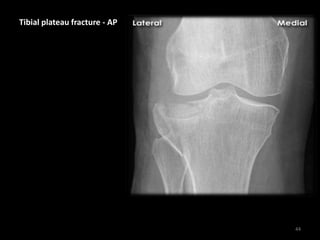

Tibial plateau fracture - AP

• Lateral tibial plateau

fracture

• The fracture fragment

is displaced and

depressed from its

normal position

(dotted line)